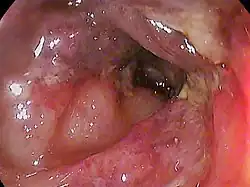

| |

| Ischemic colitis on the transverse colon of an 82 year old female | |

Endoscopic evaluation, via colonoscopy or flexible sigmoidoscopy, is the procedure of choice if the diagnosis remains unclear. Ischemic colitis has a distinctive endoscopic appearance; endoscopy can also facilitate alternate diagnoses such as infection or inflammatory bowel disease. Biopsies can be taken via endoscopy to provide more information. Visible light spectroscopy, performed using catheters placed through the 5 mm channel of the endoscope, is diagnostic (see Diagnosis).